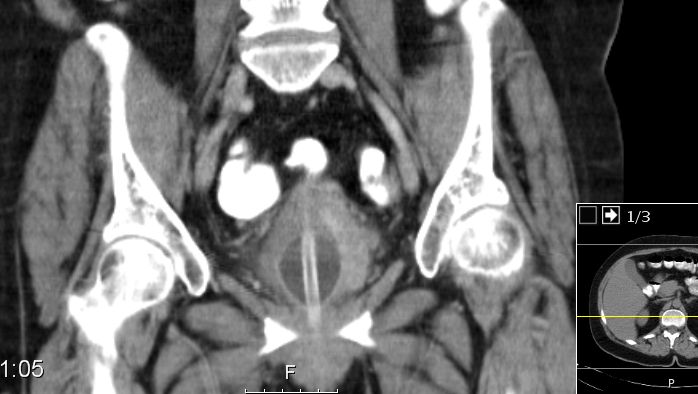

| SCC | 54-jährige geistig behinderte Frau mit einem

Plattenepithelkarzinom der Harnblase. Radikale Zystektomie und Anlage eines

Ileumconduits. Histologisch Infiltration des perivesikalen Fettgewebes. 8 Monate

später Rezidiv an der linken Beckenwand mit Beckenknocheninfiltration.![]() | |||